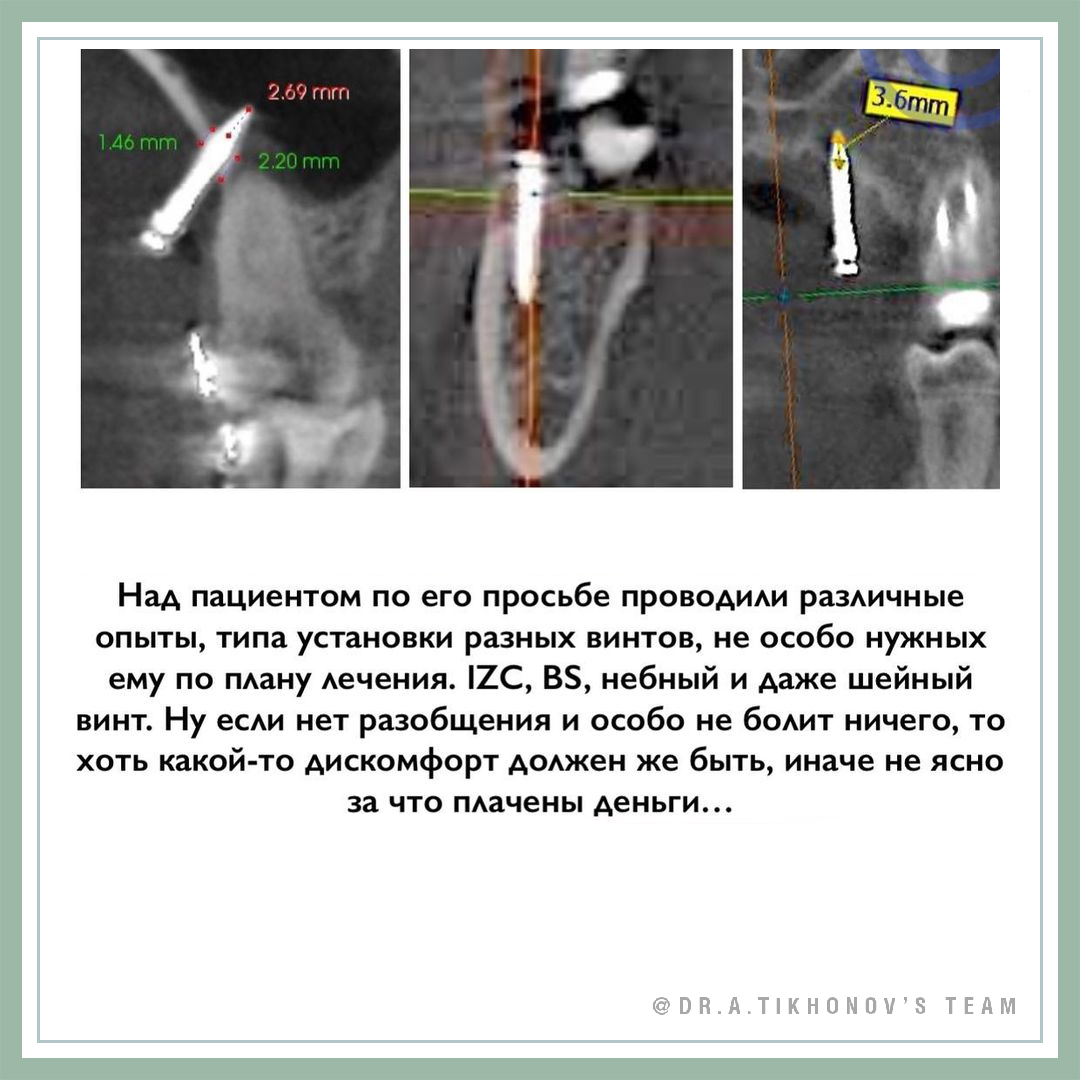

- Минивинты не так страшны. Если мешает один винт, то лучшее лекарство - поставить другой – это отвлекает.